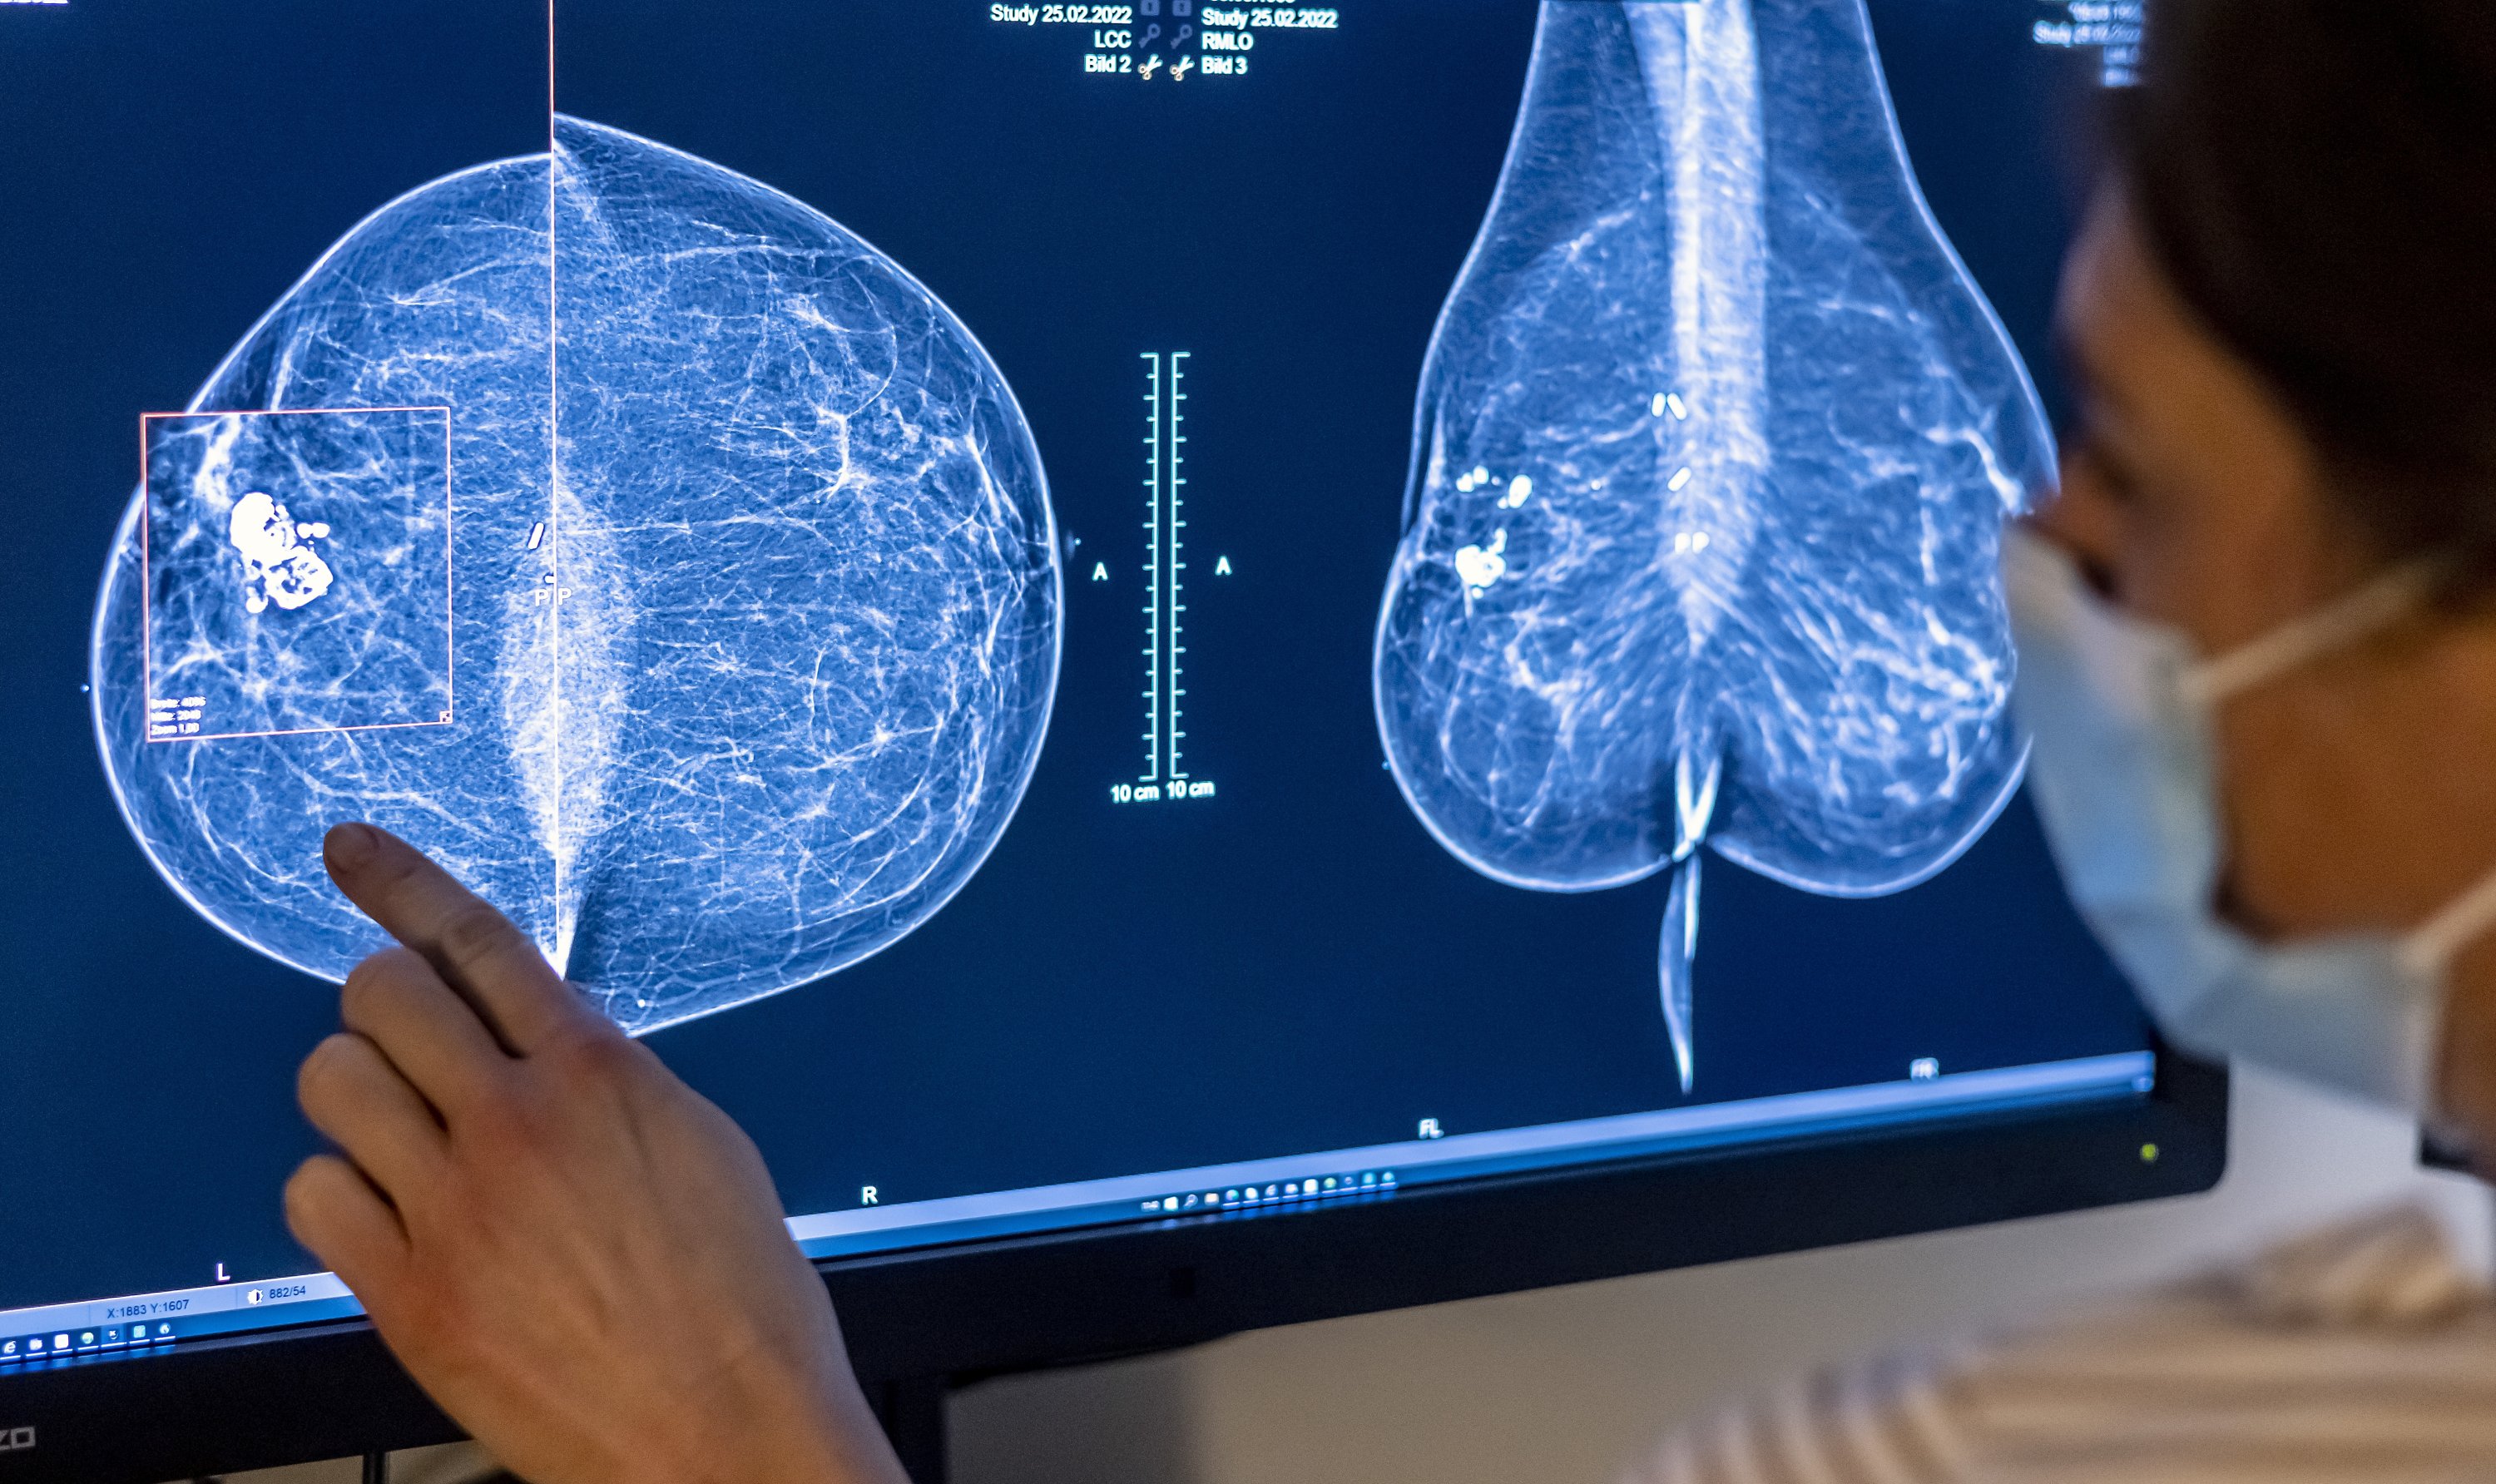

Các bác sĩ cho biết những trường hợp người bệnh dù cao tuổi mà được phát hiện bệnh sớm và điều trị kịp thời thì phương pháp điều trị sẽ đơn giản, kết quả khả quan hơn rất nhiều. Vì vậy, tầm soát ung thư sớm có ý nghĩa đặc biệt quan trọng.

Tuy nhiên, thách thức lớn nhất hiện nay vẫn là thói quen "có bệnh mới chữa". Bác sĩ Tuấn dẫn chứng các số liệu cho thấy 50 - 80% bệnh nhân nhập viện khi ung thư đã tiến triển đến giai đoạn 3 hoặc 4. Việc người dân bỏ qua tầm soát định kỳ và chỉ đi khám khi cơ thể xuất hiện triệu chứng rõ rệt đã làm mất đi thời điểm vàng để can thiệp, khiến tỷ lệ tử vong tăng cao và tạo gánh nặng chi phí lớn.

Quan trọng nhất, người dân nên tiêm vaccine phòng các bệnh có nguy cơ gây ung thư và thực hiện tầm soát theo độ tuổi ngay cả khi cơ thể bình thường. Việc phát hiện bệnh ở giai đoạn khởi phát sẽ giúp quá trình điều trị đơn giản và tăng đáng kể khả năng chữa khỏi hoàn toàn.